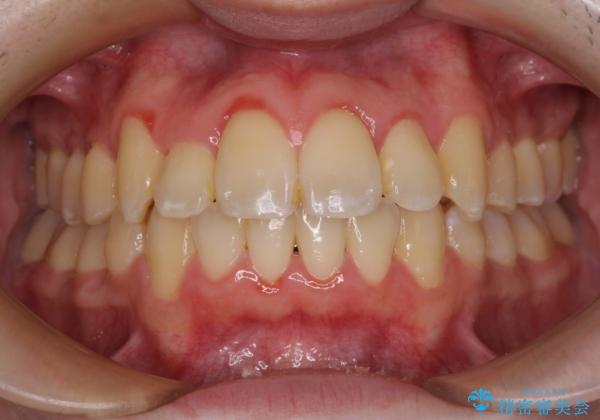

- 八重歯や奥歯の噛みにくさを気にして来院された患者様です。

前歯のクロスバイトや八重歯の他に、左右最後臼歯のシザーズバイト(鋏状咬合)が認められました。

シザーズバイト改善のために補助装置を使用しながら、ワイヤー装置にて全体の歯列を整えることとしました。